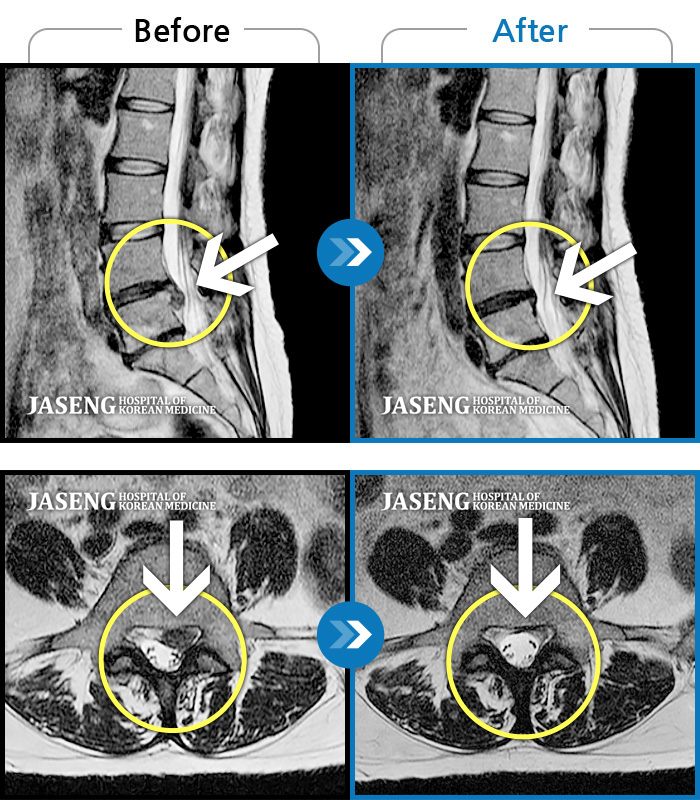

허리디스크

인천 · 조남훈 원장

허리디스크로 인한 다리 통증

촬영시기

2017.12.14 ~ 2019.06.06

2019.06.21